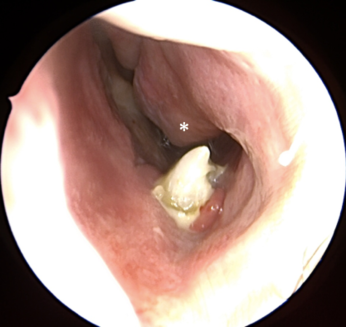

Răng thừa (b) mọc trong vòm miệng khiến cho R22 (a) mọc lệch xoay trục XQ răng toàn cảnh không thấy răng thừa do R21 (a) che khuất,(b) là R22 bị xoay trục

Hình ảnh răng thừa (a) xuất hiện rất rõ trên CT Cone Beam, (b) là hình ảnh R21

Hình 3: Tính ưu việt của CT Cone Beam trong chẩn đoán răng thừa